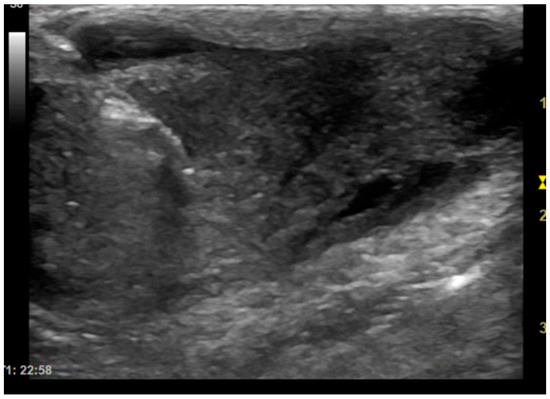

This study investigates the usefulness of extemporaneous cytological examination performed during imaging-guided biopsies in dogs and cats. In veterinary diagnostics, imaging techniques such as ultrasound and computed tomography are essential for identifying lesions, but they cannot distinguish between inflammatory and neoplastic processes. Biopsies [...] Read more.

This study investigates the usefulness of extemporaneous cytological examination performed during imaging-guided biopsies in dogs and cats. In veterinary diagnostics, imaging techniques such as ultrasound and computed tomography are essential for identifying lesions, but they cannot distinguish between inflammatory and neoplastic processes. Biopsies are therefore required, and this study explores whether immediate cytological evaluation of tissue cores, rolled onto slides and examined under a microscope, can help determine sample adequacy and reduce the number of biopsies needed. Seventy-nine animals with soft tissue or bone masses underwent ultrasound or CT-guided biopsies, followed by extemporaneous cytology and histopathological analysis. Cellular material representative of the lesion was identified in 81.1% of cases, allowing clinicians to conclude the procedure without further sampling. The diagnostic accuracy of cytology compared to histology was 68.3%, with particularly high accuracy for lipomas, melanomas, and mast cell tumors. When excluding non-diagnostic samples due to poor preparation or lesion characteristics, the accuracy reaches 92.1%. These findings suggest that extemporaneous cytology is a useful tool for verifying sample adequacy in real time, potentially reducing procedural risks and improving diagnostic efficiency. While histology remains the gold standard, this method offers immediate feedback and may enhance clinical decision-making in veterinary interventional diagnostics. Full article